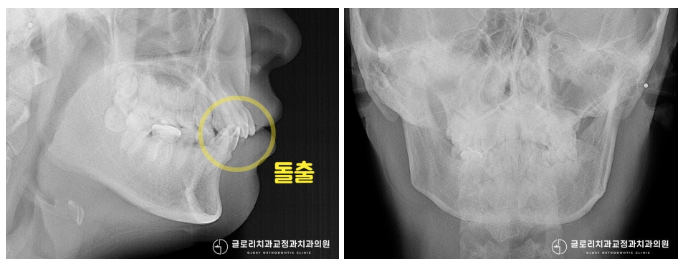

더 자세한 진단을 위해

방사선 촬영을 진행해보니

약간의 돌출이 확인되었습니다.

실제로 측면에서 촬영한 사진을 보면

전방으로 뻗쳐 있는 듯한 앞니가 관찰 되는데요.

망우역치과 에서는 총생과 돌출,

두가지를 개선하는 방향으로

전체적인 치료 계획을 세우기로 했습니다.